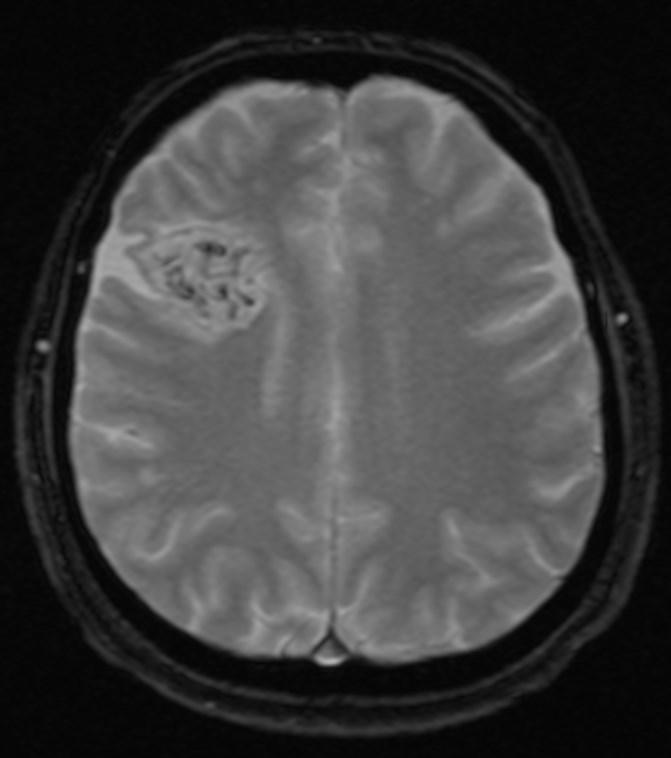

Answer: Primary hydatid cyst of right frontal lobe.

MR images revealed Gharbi type V hydatid cysts in right frontal lobe.

Gharbi classified hydatid cyst ultrasonographic images into 5 types: Type 1, walled, unilocular, anechoic; type 2, separated membranes; type 3, multisepta, daughter vesicles; type 4, heterogenic, hypo-hyperechogenic; type 5, calcification of a section of the wall or completely calcified (4). The cysts characteristically have three components: Pericyst, Exocyst, and Endocyst.